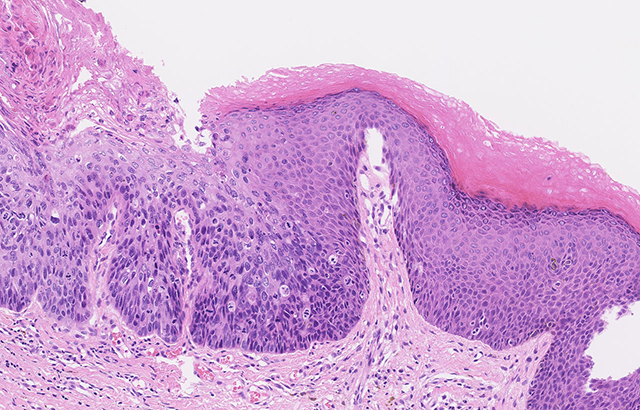

Microscope image of abnormal cells within the anus